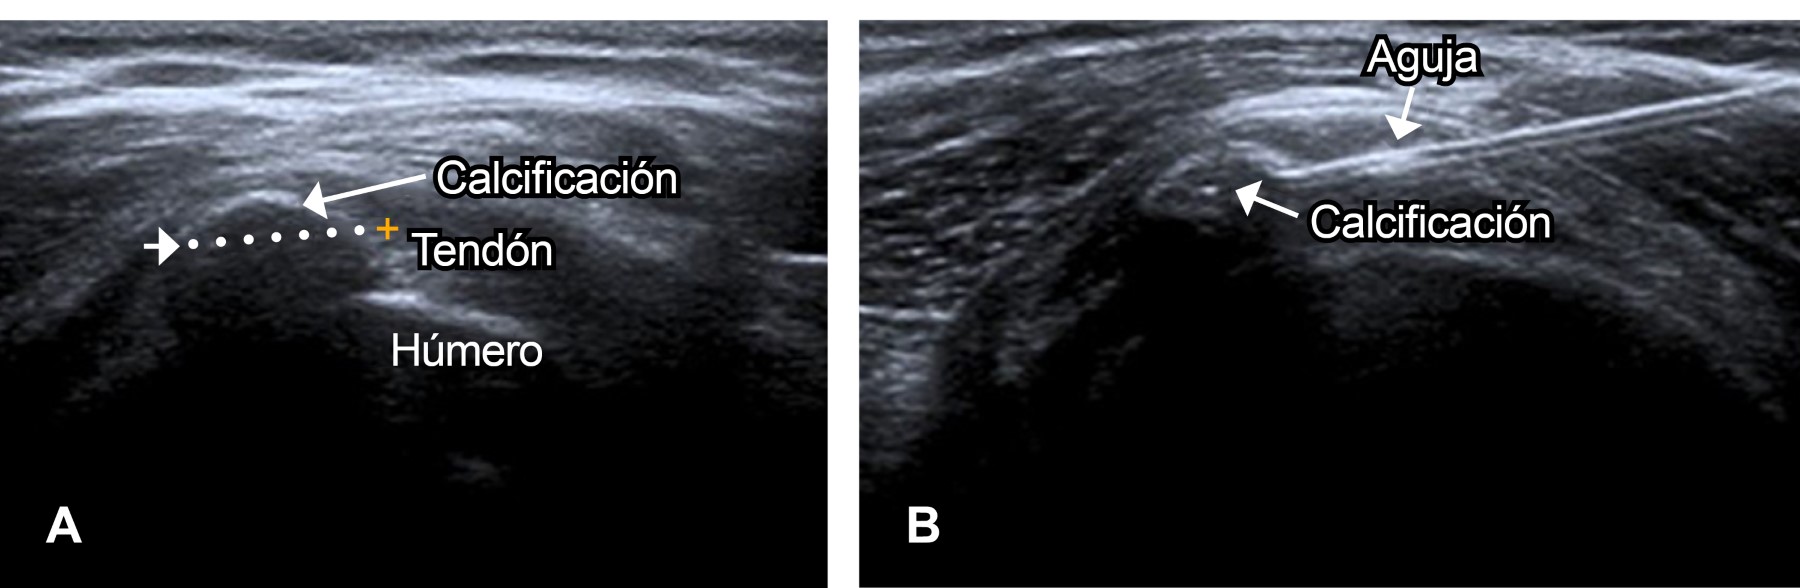

Las punciones de las formaciones cálcicas no son algo nuevo, en el año 1913, Flint describió esta técnica al igual que la reportó Codman7 en 1934. Desde los años 50 del siglo pasado, varios autores recomendaban las punciones a ciegas de los depósitos de calcio con una alta tasa de éxitos (85%) defendiendo a la punzadura de la calcificación y no la exéresis de la misma.21,22 Depalma y Kruper13 popularizaron el uso de punciones a ciegas sin identificación radiológica con buenos resultados (72%). En el año 1996, Farin y cols.1 construyeron un estudio donde realizaron punciones y aspiraciones guiadas por ecografía demostrando mejoría de los síntomas en 75% de los casos. En 2014, Gatt y asociados23 reportaron que el uso de punciones y aspiración genera mejoría de los síntomas en el 88% de los pacientes. En 2013, De White24 comparó la punción aspiración dirigida por ultrasonido contra el uso de esteroides intralesionales (Figura 3), reportando que la primera tenía mejores resultados (83%) que la segunda (63%). Castillo y colaboradores12 además reportan que la incisión y aspiración conducida por ultrasonido, con un seguimiento de dos años, muestra la desaparición de la sintomatología en 98% con evidencia radiológica de desaparición de la calcificación del 70%.

Figura 2

Figura 3